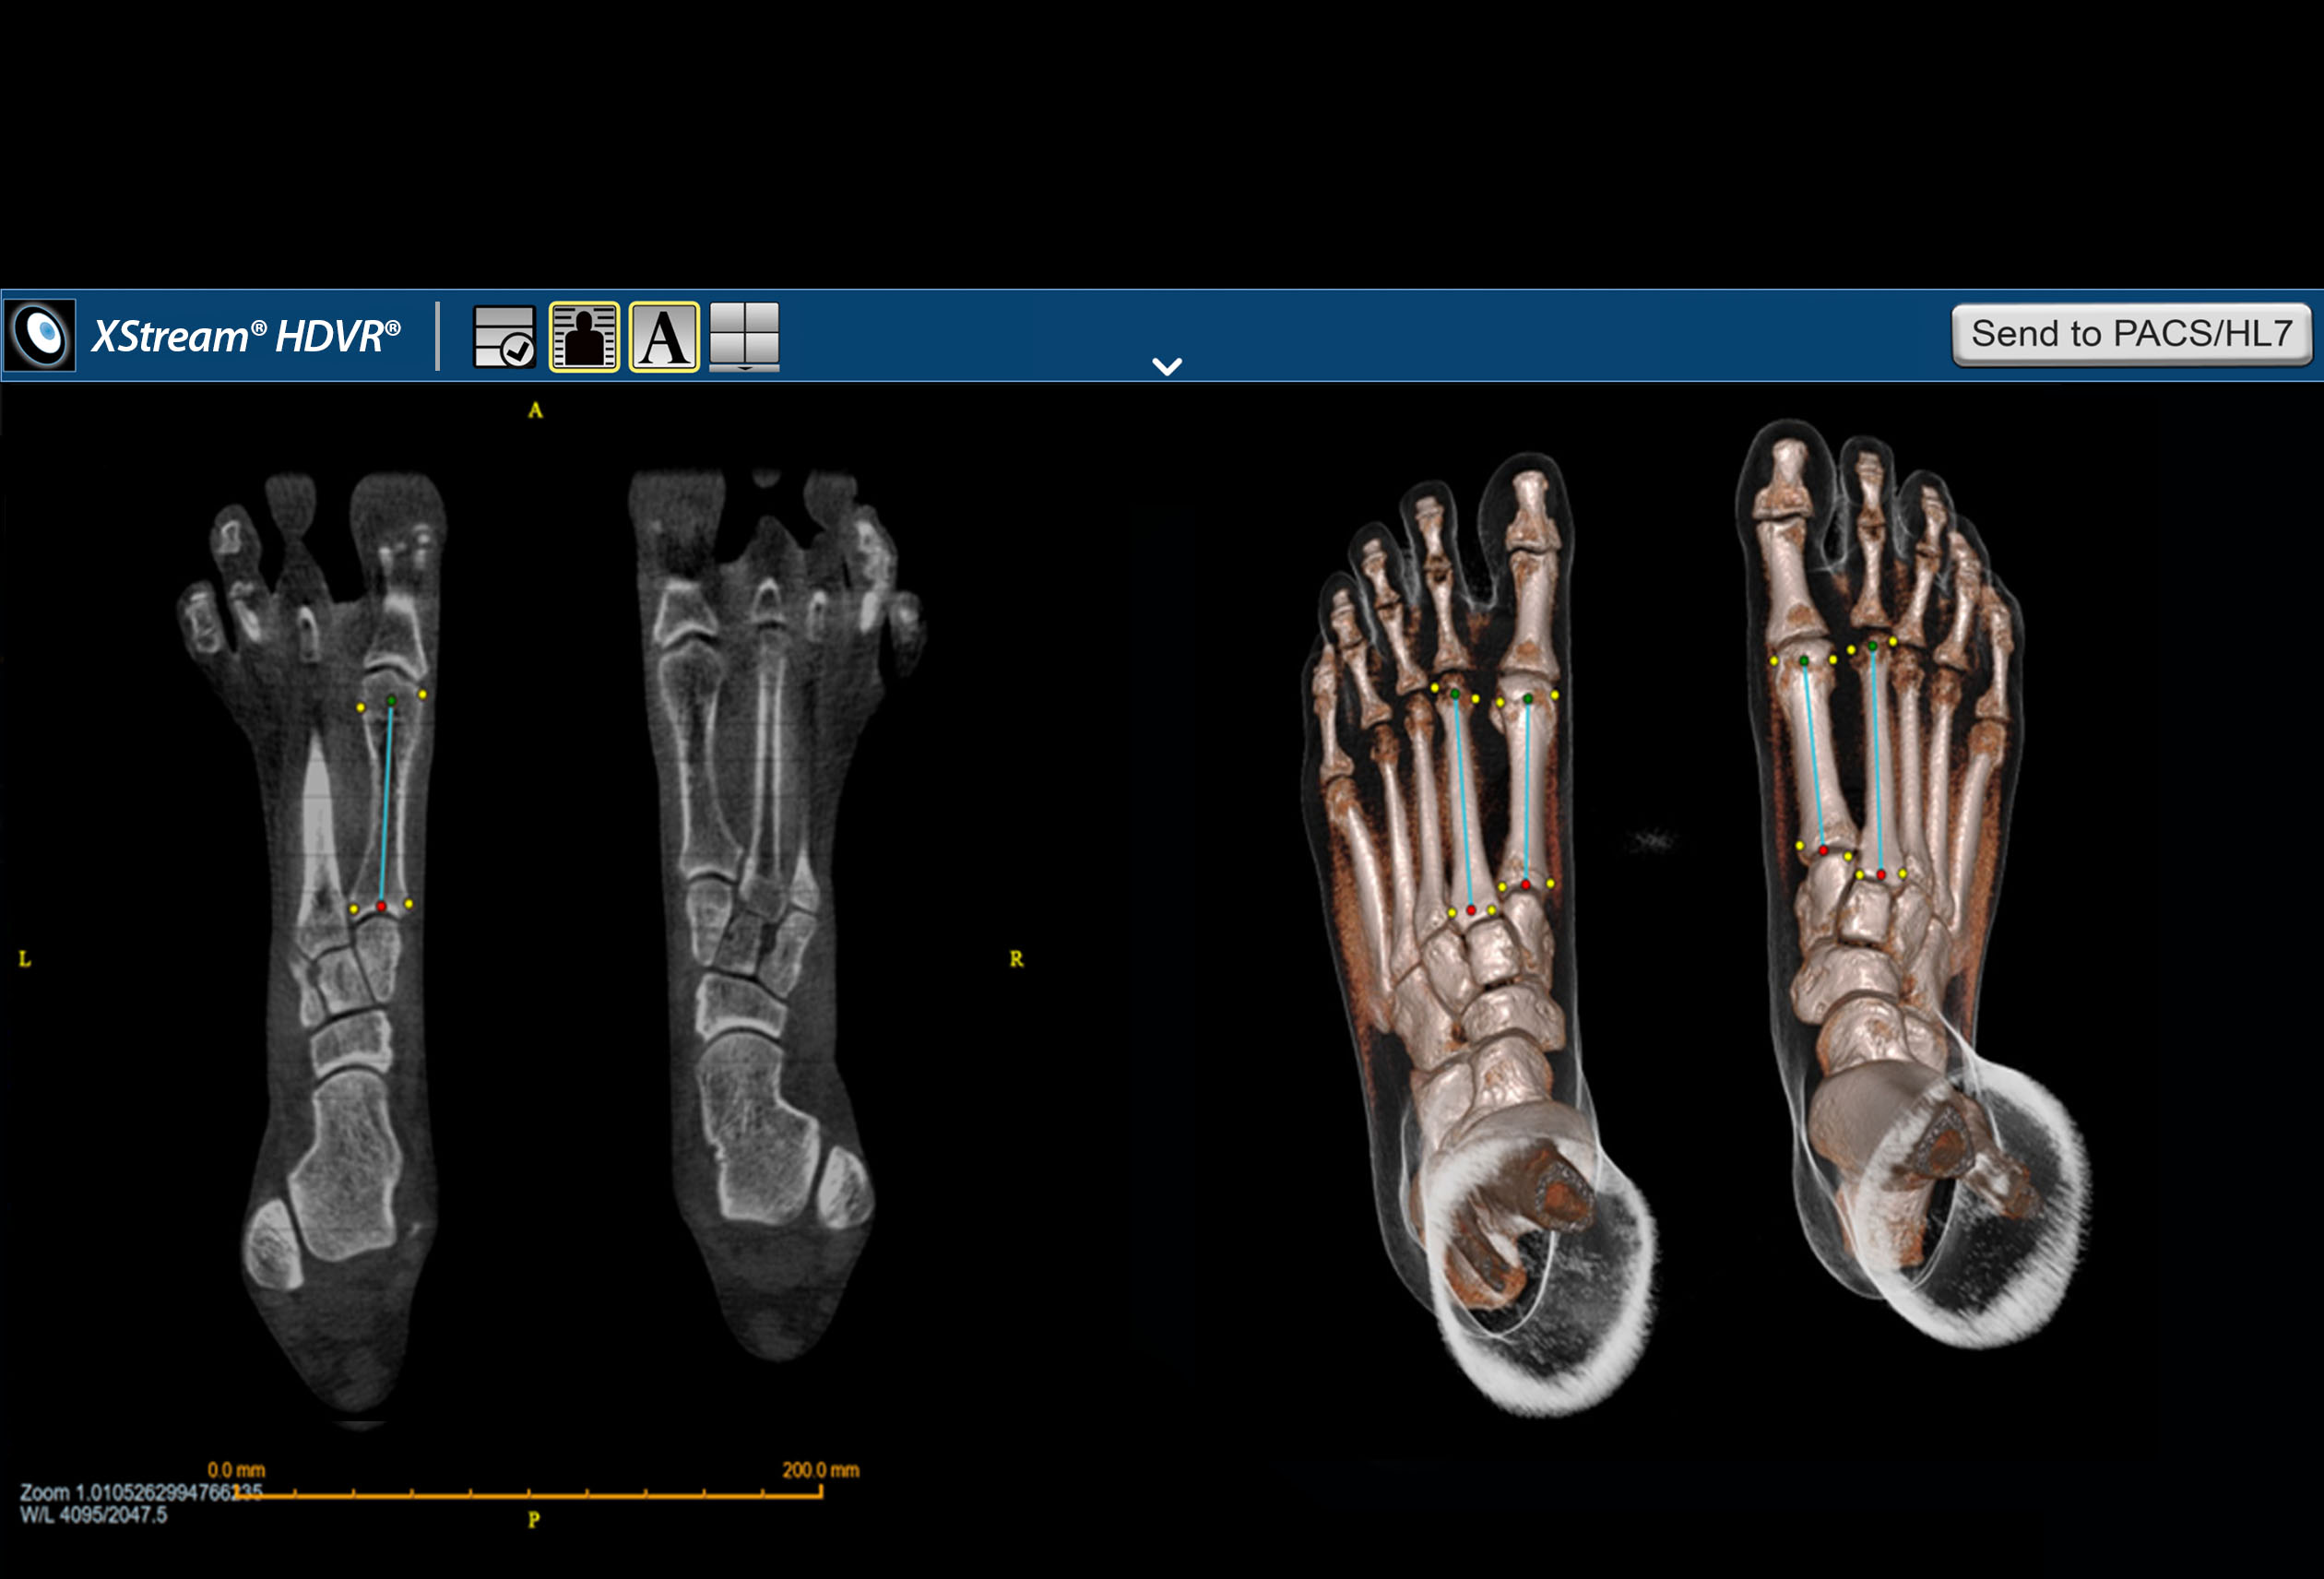

F.A.S.T. Ortho Workflow

F.A.S.T. Ortho Workflow